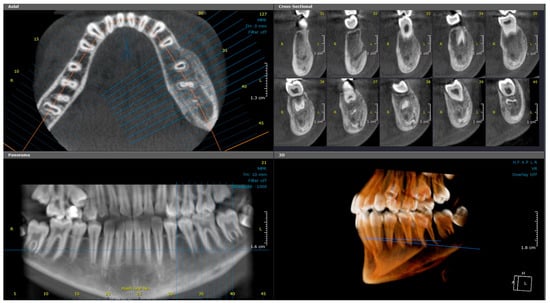

2.2. Case 2

2.2.1. History and Clinical Examination

2.2.2. Radiographic Examination

| 2 | 9 | Right mandible (#33–#47, crossing midline) | Patchy sclerotic and radiolucent lesion, mandibular expansion, double cortex | Viable bone with osteoblastic rimming, no bacterial colonies | Multiple antibiotics, extractions, NSAIDs | CNO based on imaging, histology, and clinical course | NSAIDs only; progressive improvement | Gradual resolution with NSAIDs |